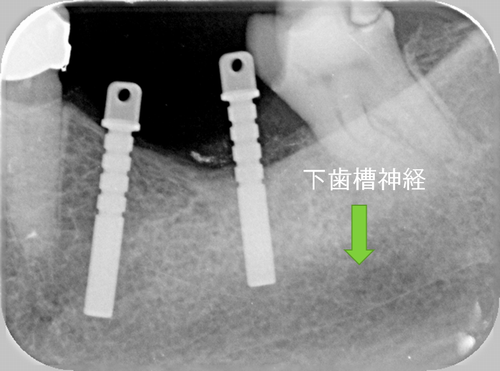

この患者様は、右上の奥歯の歯茎から出血してくるとのことで来院されました。歯周組織検査とレントゲンで診断を行った結果、重度の歯槽膿漏が認められ、保存不可能の為、抜歯になると伝えたところ、入れ歯は絶対に嫌だと言われたので、インプラント治療となりました。CT撮影を行ったところ、上顎洞底までの距離が3ミリ程度しかなかったのですが、骨が固く、フィクスチャーの一次固定が良好だったので、開窓法による上顎洞底挙上術とフィクスチャーの埋入を同時に行いました。約10カ月後に二次手術を行い、上部構造をセットしました。また、右下の臼歯部のブリッジにも大きな二次カリエスが認められ、7番の遠心根が抜歯になり、6番、7番にインプラント治療をしました。